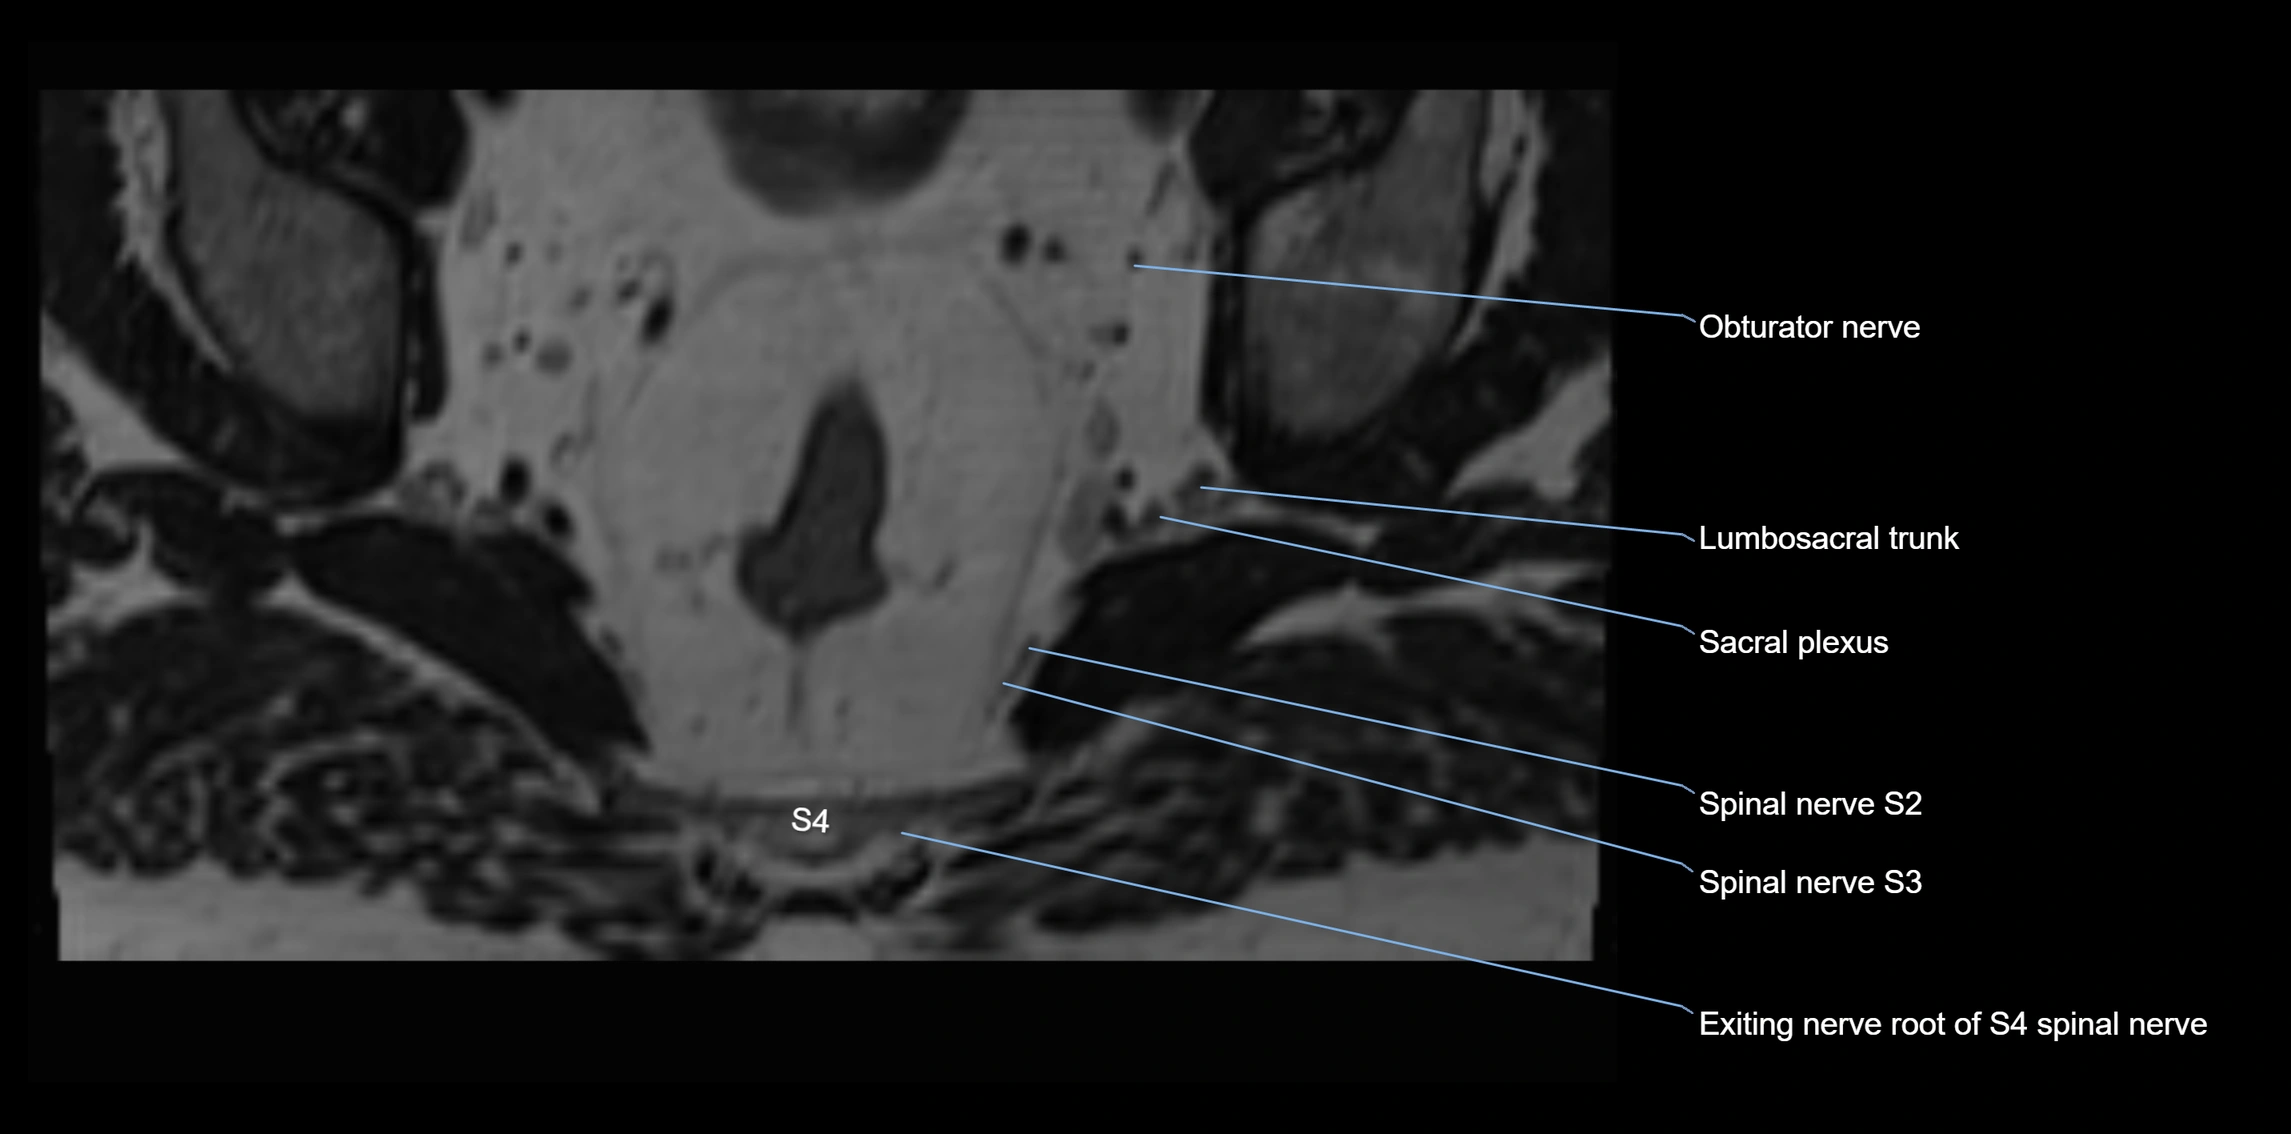

MRI Appearance

T1-weighted images:

• Nerve appears as a very thin low-to-intermediate signal intensity structure

• Surrounded by bright fat, aiding visualization

T2-weighted images:

• Nerve shows intermediate to mildly hyperintense signal compared to muscle

• Pathological involvement appears brighter

STIR (Short Tau Inversion Recovery):

• Normal nerve appears dark

• Inflamed or entrapped nerve appears bright hyperintense

T1 Fat-Sat Post-Contrast:

• Normal nerve enhances minimally

• Pathologic nerve (neuritis, entrapment, tumor infiltration) shows focal or diffuse enhancement

3D T2 SPACE / CISS:

• Nerve appears intermediate to mildly hyperintense compared to muscle

• Surrounded by bright fat or CSF, improving visualization

• Best sequence for mapping small pelvic nerves such as the anococcygeal